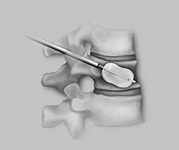

- In allen anderen Fällen wird durch einen kleinen Hautschnitt von 2-3 cm der Wirbelkanal dargestellt.

- Unter dem Operationsmikroskop wird der Nerv weggehalten und das herausgesprengte Bandscheibenmaterial entfernt.